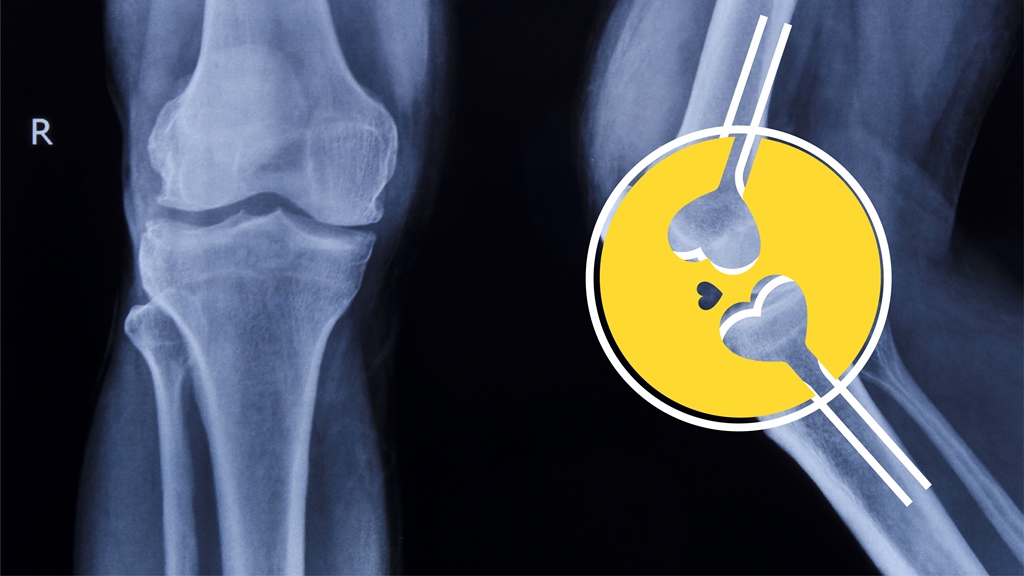

María del Pilar, es una Ortopedista muy especial, ya que su especialidad es la Ortopedia y traumatología en niños, una actividad que le permitió soñar con independizarse y crear su imagen, el desafío era construir su marca con los ingredientes que más la representan: energía, amor y cuidado con el que asume su formación. Este es el desarrollo de su marca.